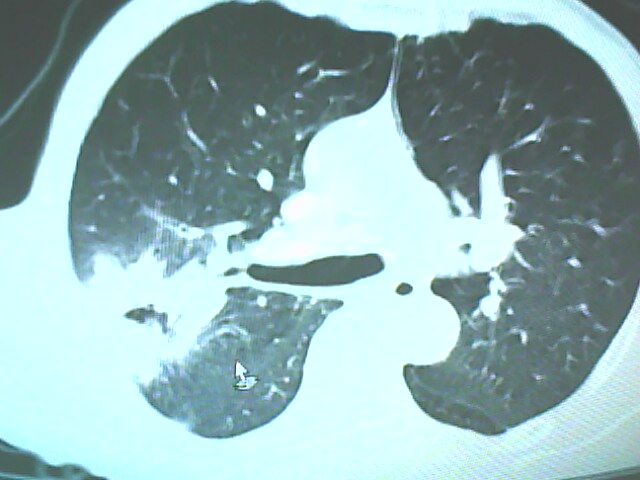

患者,男,66岁,以咳嗽、咳痰伴胸痛来就诊。

胸片提示右上肺占位病变。请各位老师看看ct。

考虑癌性空洞可能性大,空洞内壁不规则,病灶周围模糊,分叶、有毛刺

空洞内壁不规则,病灶周围模糊,分叶、毛刺呈日光放射状,突然截断,支持考虑癌性空洞

考虑右肺上叶后段周围型肺癌并癌性空洞形成。

考虑癌性空洞可能性大,内壁不规则,洞壁薄厚不均呈结节状突起,边缘模糊,分叶,毛刺

右上肺后段肺癌:

典型癌性空洞(偏心性,壁厚薄不均,内壁不光整),周围毛刺较僵硬,且有刺突征和血管聚集征